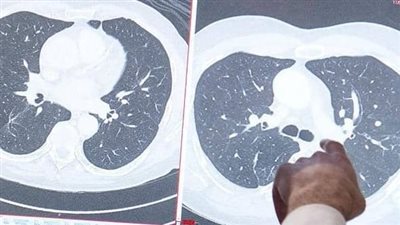

الفرق بين الكتل الحميدة والخبيثة في الثدي

معظم أورام الثدي عبارة عن تكيسات حميدة، خاصة عند النساء الأصغر سنًا، قد يختلف الحجم والحنان مع الدورة الشهرية، عندما تكون الكتل طرية، فمن المرجح أن تكون حميدة، ولكن حوالي 10 في المائة من سرطانات الثدي تسبب ألمًا أو إيلامًا في الثدي.

تميل السرطانات إلى الشعور بقوة أكبر من الكيسات الحميدة والأورام الغدية الليفية، يمكن تقريب الجماهير الحميدة والخبيثة والمتحركة فقط عندما تكون السرطانات متقدمة جدًا، يتم تثبيتها على الجلد أو جدار الصدر الأساسي، ولا يمكن تحريكها.